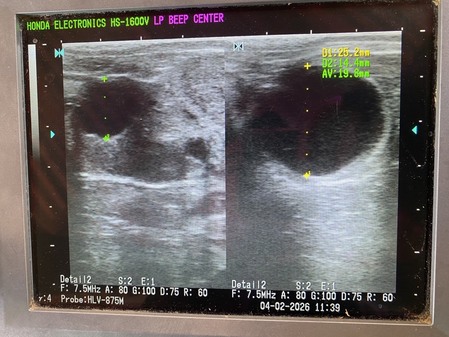

ศูนย์วิจัยการผสมเทียมและเทคโนโลยีชีวภาพนครราชสีมา บูรณาการร่วมกับ ศูนย์วิจัยและบำรุงพันธุ์สัตว์ชัยภูมิ และ ศูนย์วิจัยและพัฒนาโคเนื้อ ดำเนินการตรวจท้อง ตรวจระบบสืบพันธุ์ พร้อมทั้งแก้ไขปัญหาการผสมติดยากและผสมเทียมแม่โคเนื้อ ในการนี้ นายสมพิศ รักงาม ผู้อำนวยการศูนย์วิจัยและบำรุงพันธุ์สัตว์ชัยภูมิ ได้เข้าร่วมปฏิบัติงานด้วยตนเอง เพื่อให้การสนับสนุน ให้คำแนะนำ และติดตามผลการดำเนินงานอย่างใกล้ชิด อันเป็นการเสริมสร้างประสิทธิภาพในการพัฒนาระบบสืบพันธุ์โคเนื้อและเพิ่มอัตราความสำเร็จในการผสมเทียม ณ ศูนย์วิจัยและพัฒนาโคเนื้อ อำเภอลำสนธิ จังหวัดลพบุรี